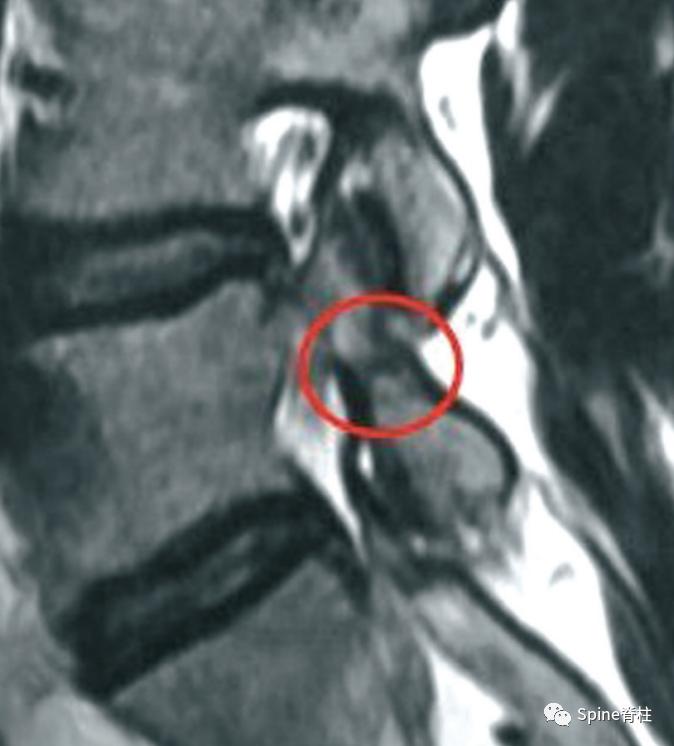

MRI提示的峡部裂(红圈)

有研究发现磁共振上 椎弓根出现T2高信号改变是青少年和儿童峡部裂的早期诊断征象 。同时, 存在椎弓根高信号改变也是保守治疗后能达到骨性愈合的良好预测指标 (也就是说存在T2椎弓根右高信号改变的峡部裂患者,其峡部裂经保守治疗愈合的可能性大) 。